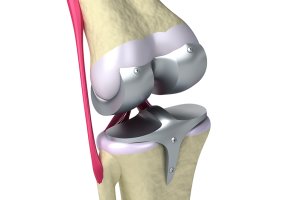

건강기능식품의 원료로 사용할 때의 콘드로이틴은 콘드로이틴 황산염 형태를 말하며 콘드로이친은 관절 보충제의 구성성분으로 많이 알려져 있습니다. 콘드로이친 자체가 관절을 지지해주는 연골의 성분이며 또한 콘드로이친은 콘드린의 유도체이기도 한데, 이 콘드린이라는 성분은 동물의 연골을 오래 물에 끓였을 때 녹아 나옵니다. 따라서 연골 성분을 직접 체내에 보충해줄 수 있다는 기대로 콘드로이친이 관절영양제의 성분으로 관심을 받게 된 것입니다.

보통 사람의 연골은 60%~80%가 수분으로 구성되어 있고 그 밖에 콜라겐, 글루코사민, 콘드로이친, 히알루론산으로 이루어져 있습니다. 이 중 콘드로이친은 연골의 수분을 유지해 주고 뼈와 연골과 같은 조직을 형성하며 구성하는 성분입니다. 나이가 들어감에 따라 감소하는 콘드로이친은 20대부터 서서히 줄어들기 시작해 40대가 되면 20대의 절반으로 줄어들고 70대가 되면 75%가 줄어들면서 시간이 지나면 점점 더 없어진다고 합니다.